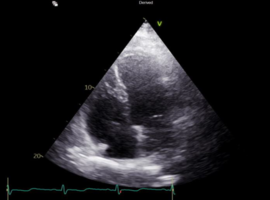

Citation: Amara M, Feld Y. A Rare Case of Takotsubo Cardiomyopathy in a 51-year-old Male Patient. Case Rep Clin Cardiol J. 2026; 6(1): 168.